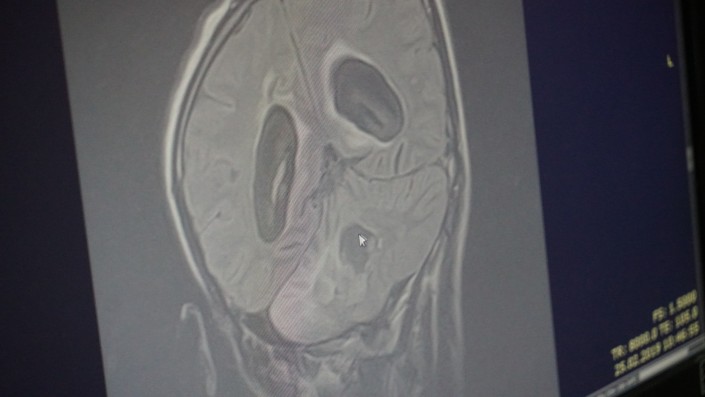

По совету соседа они сделали МРТ (магнитно-резонансная томография). Оказалось, что у парня опухоль головного мозга, и довольно внушительных размеров. Его сразу же отправили на экстренную операцию.

Ему уже дважды делали операцию, удаляли опухоль в головном мозге. Третий раз делать ему операцию врачи отказались.

"В прошлом году 7 марта нам сделали вторую операцию и сказали: все, больше делать нельзя, иначе весь мозг придется удалять, третьей операции он не выдержит", - говорит мать.